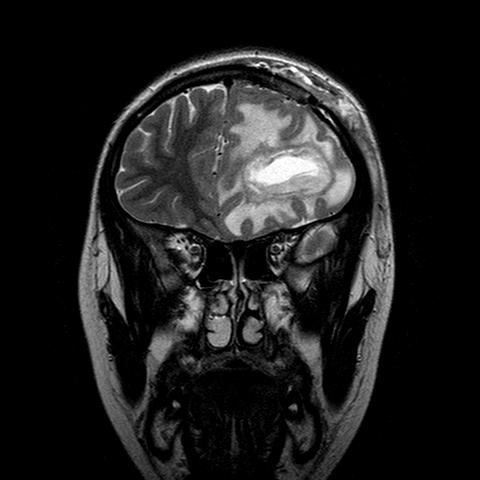

Nel decorso post operatorio la ragazza si mantiene asintomatica e gli indici di flogosi si riducono progressivamente. In 18^ giornata si ripete RMN di controllo (Figura 2) che mostra una lieve riduzione della lesione (diametro 50 x 3,9 x 3 mm) mentre persiste sostanzialmente invariato l�edema perilesionale, con spostamento della linea mediana.

Figura 2. Lesione in sede frontale iperintensa nelle sequenze T2 di dimensioni 5x3,9x3 cm compatibile con ascesso cerebrale, circondato da marcato edema perilesionale. Deviazione della linea mediana verso dx di circa 1.1 cm e in corrispondenza del corpo dei ventricoli di circa 7 mm. Raccolta extracerebrale in sede frontale sinistra di dimensioni 1.4x4x3.5 cm compatibile con raccolta. Impregnazione meningea frontale sinistra.